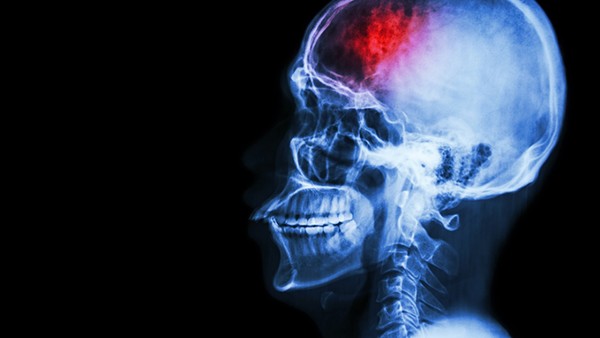

癫痫是由脑神经异常放电引起的。

创伤后,癫痫的病因主要是颅脑创伤、昏迷时间长、脑损伤重、发病率高。